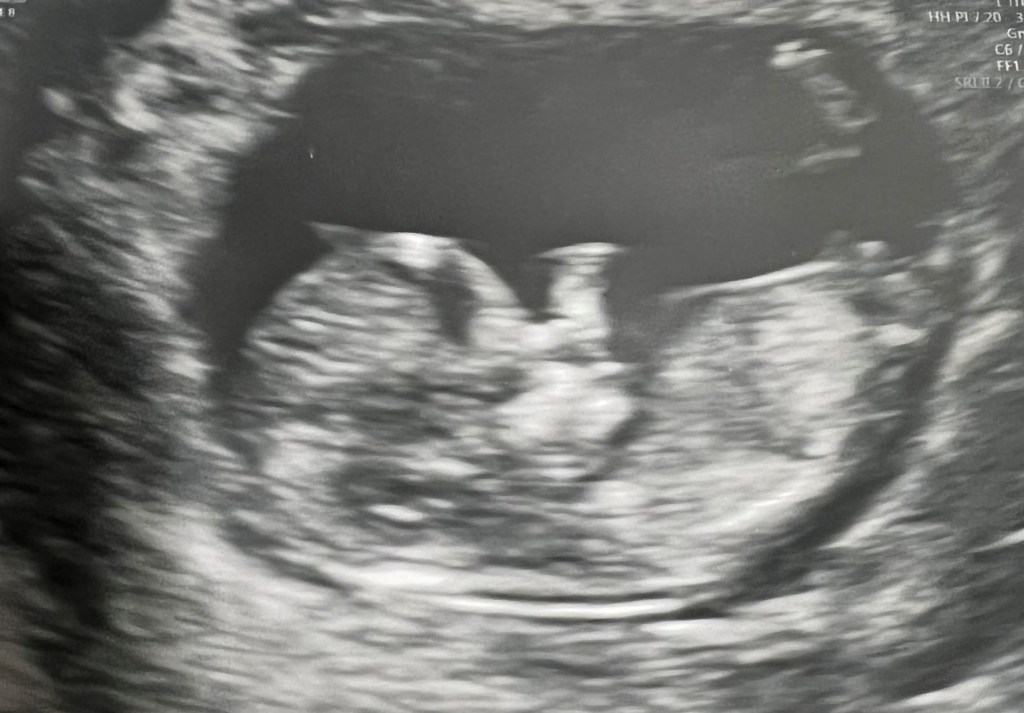

And as of October 2020, we joined the ranks of families with children under five. Enter Maddie.

For those who can do the math, we got pregnant pre-pandemic and gave birth while lockdown was in full swing. While the vaccine for this age group is in the works, our protocols have not changed. In fact, over the last few months, we’ve tightened our lockdown and limited our exposure. Enter baby boy Younger, due this August.